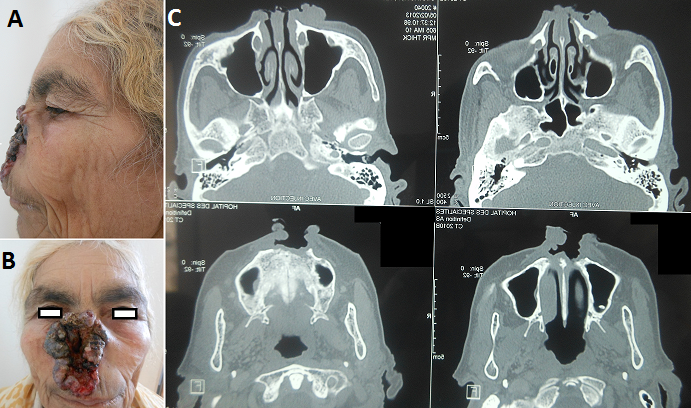

Tumeur noire de la pyramide nasale

Les tumeurs historiques (< 1 % des carcinomes cutanés) sont des tumeurs géantes, de diamètre supérieur à 10 cm, et de longue durée d'évolution. Le CBC infiltrant est un carcinome mutilant de mauvais pronostic. Il représente 40 % des carcinomes de la pointe et l'aile du nez. Les CBC de la pointe nasale, ont une histologie agressive confortant la chirurgie comme le traitement de choix. Le traitement consiste en une chirurgie de reconstruction avec un lambeau de transposition de type Limberg à pédicule supérieur, pris sur l'auvent nasal et la joue, ou une greffe de peau totale. La place de technique de chirurgie micrographique dans cette localisation mérite d'être soulignée. Nous rapportons l'observation de la patiente BM, 64 ans présentant une tumeur ulcéro-bourgeonnante du nez douloureuse, nauséabonde saignant au contact évoluant depuis 4 ans. L'examen clinique trouve une tumeur ulcéro-bourgeonnante croûteuse noirâtre perlée mesurant 10cm sur 6cm au dépend de la pyramide nasale mettant à nu la muqueuse nasale. La base est représentée par le plancher de la muqueuse nasale. L'histologie de la tumeur médio-faciale a objectivé un tissu ulcéré siège d'une prolifération carcinomateuse infiltrant le derme, les cellules basaloides munies de noyaux peu atypiques, un cytoplasme basophile et un stroma fibro-inflammatoire, en faveur d'un CBC infiltrant. Le bilan d'extension objective des adénopathies jugulaires droites d'allure inflammatoires, un processus tumoral infiltrant avec envahissement du tissu sous-cutané adjacent et lyse osseuse (os propre du nez et maxillaire supérieur). Une radiothérapie suivie d'une chirurgie de réparation par lambeau de rotation frontonasal ont été proposée.